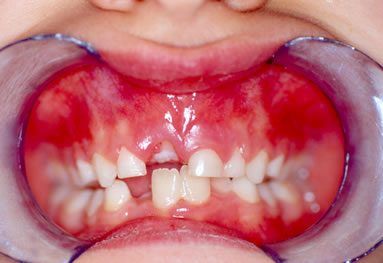

I° Caso- La piccola S.T. di anni 4 è giunta alla nostra osservazione per una visita ortodontica mandata dal suo pediatra di famiglia. All'anamnesi risultava che la bambina respirava prevalentemente con la bocca e durante la notte russava e andava i apnea. All'esame clinico ortodontico la bambina presentava un morso inverso anteriore con palato ogivale (Figura 1).E' stato richiesto quindi un monitoraggio cardio-respiratorio che è stato eseguito con un poly-mesam 8 canali portatile. Tale esame ha evidenziato un RDI =13 associato a forte russamento (Figura 2). Sulla radiografia del cranio in proiezione latero-laterale è stata eseguita l'analisi cefalometrica che ha messo in evidenza una I classe scheletrica con tendenza alla III in soggetto ipodivergente. In considerazione del morso inverso e del palato ogivale, si è deciso di applicare un espansore rapido palatale con ganci per maschera di Del aire (Figura 3). Ottenuta l'apertura della sutura palatina è stata applicata la Maschera facciale di Delaire per la trazione postero-anteriore del mascellare superiore. Dopo 2 mesi dall'inizio della terapia è stato eseguito un monitoraggio cardio-respiratorio di controllo che ha messo in evidenza un RDI= 5 con riduzione del russamento rumoroso (Figura 4). Dopo 6 mesi, ottenuta la correzione del morso inverso e del palato ogivale, una volta rimosso l'espansore rapido e la maschera facciale, è stato applicato un apparecchio funzionale di III classe come mantenimento. La correzione della malocclusione ha coinciso con il miglioramento dei sintomi respiratori come anche riferito dalla madre.